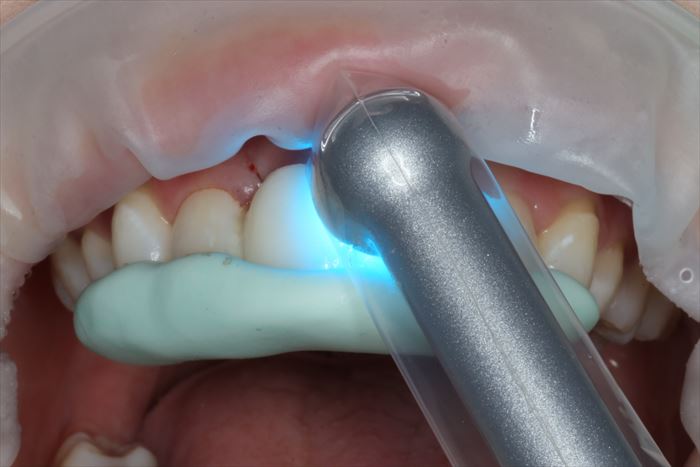

幸運にも元々の仮歯を加工して使える状態でしたので、位置付け用シリコンジグを使用して両サイドの歯と固定します。

青い光を照射して透明なレジンを用いて両サイドの歯に接着している場面です。